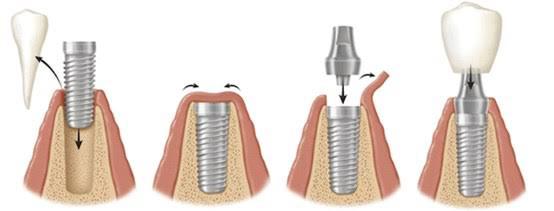

Etapele tratamentului cu implant denta

2. Inserarea implantului

Procedură chirurgicală realizată sub anestezie locală, în condiții de siguranță.

3. Perioada de vindecare (osteointegrare)

Implantul se integrează progresiv în os.

4. Reabilitarea protetică

Aplicarea lucrării definitive, adaptată funcțional și estetic.